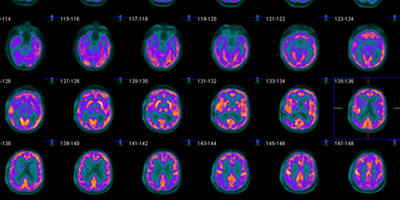

New IDEAS Study

The New IDEAS Study is designed to evaluate the use of PET scans in diverse populations living with dementia and Alzheimer's.

Learn More